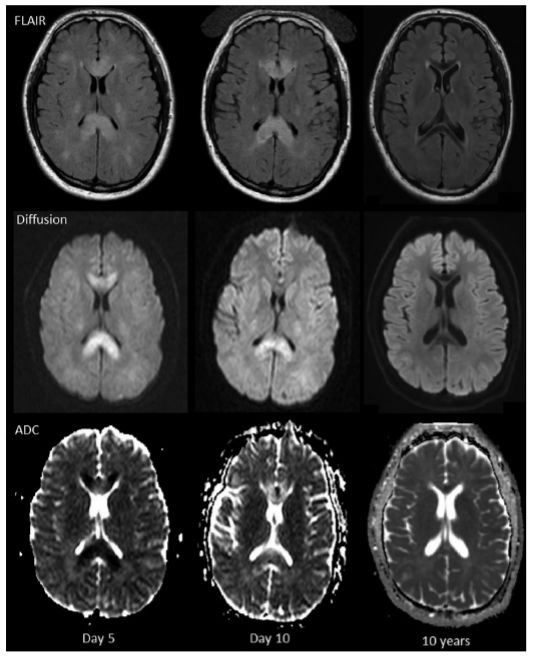

8例患者首次MRI成像的FLAIR和T2序列显示高信号(图1)。其中,5例高信号出现在胼胝体和皮质下白质、2例仅在皮质下白质和1例在脑室周围白质内。10天内再次行MRI成像,5例显示白质区水肿较前加重。

图1. MRI轴位FLAIR、diffusion和ADC成像提示整个胼胝体及双侧皮质下白质区高信号和弥散受限。

8例患者的MRI-DWI成像显示弥散受限,提示细胞毒性脑水肿。7例弥散受限主要在胼胝体和皮质下白质区,与FLAIR异常信号区相对应。随访时发现弥散受限程度随着时间而消失,比FLAIR及T2序列异常变化快(图2)。